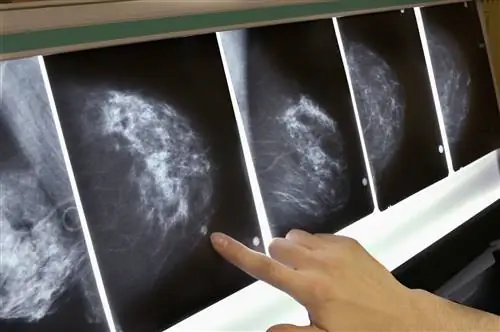

Внешний вид на маммограмме

Раковые и доброкачественные новообразования могут выглядеть одинаково на маммограмме. Однако некоторые результаты чаще встречаются в одном, чем в другом.

Важно отметить, что около 20% случаев рака молочной железы не обнаруживаются даже при скрининговой маммографии. С другой стороны, доброкачественные изменения молочной железы иногда выглядят как рак.

Масса из-за рака

Опухоль рака молочной железы на маммограмме часто имеет неправильную форму. Края не выглядят гладкими. Колючее образование молочной железы с шипами, отходящими от основной массы, является сильным сигналом, указывающим на рак.

На самом деле, слово «рак» происходит от того, как эти крабовидные расширения выглядят, когда они проникают в близлежащие ткани. Края образования также могут казаться нечеткими или нечеткими.

Раки часто кажутся яркими при взгляде на маммограммы. Область вокруг массы может быть искажена. Также могут быть видны кальцификации молочной железы (отложения кальция в груди), особенно когда они сгруппированы в кластеры.

Масса из-за благоприятных условий

На маммограмме доброкачественные опухоли часто выглядят круглыми или овальными (эллипсовидными) с четкими, хорошо очерченными краями.